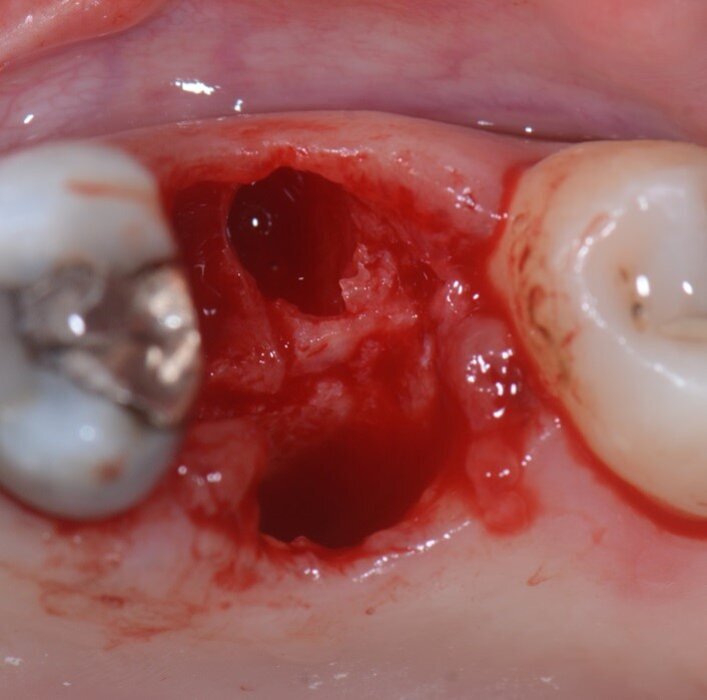

La tecnica dell’inibizione periostale modificata (MPI) mira non solo a mantenere intatta la corticale vestibolare impedendo al periostio di intervenire sulla guarigione della ferita, ma anche ad aumentarne lo spessore incollando in singolo o doppio strato una lamina corticale soft spessa 0,5 mm (Osteobiol, Tecnoss). L’utilizzo della lamina corticale suggerisce l’applicazione di questa tecnica anche nei casi in cui il piatto vestibolare fosse in tutto o in parte assente. Il caso mostrato in questo articolo rappresenta il pilota di una modifica della tecnica di inibizione periostale: è pertinente all’estrazione di un primo molare superiore destro a causa di un riassorbimento interno che rendeva il dente non trattabile (Figg. 1a, 1b), la cresta alveolare presentava un sottile strato di osso corticale sia dal lato buccale che da quello linguale.

Figg. 1a, 1b - Elemento dentale n. 16 che necessita l’estrazione.

Fig. 3 -Alveolo post estrattivo.